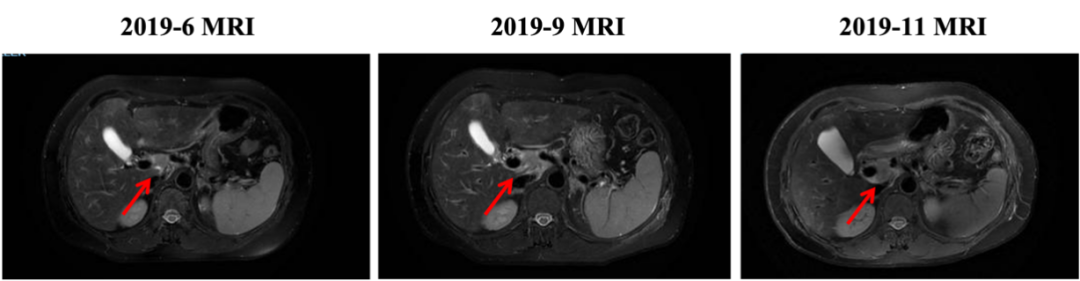

▌三线治疗:

入组MO28231临床试验,于2016-12-1开始行T-DM1治疗,具体:T-DM1 3.6mg/kg 237.6mg d1,Q21d。最佳评效PR。肝门区淋巴结自2019-6出现,逐渐增大,2019-11增大至29*22mm,考虑转移,判定为新发病灶PD出组,共治疗48周期,PD时间为2019-6,PFS为30月。不良反应:胆红素升高1级,血小板下降1级,疲劳1级,鼻出血1-2级,关节僵硬1级,手足麻木1级。

图4. 三线治疗